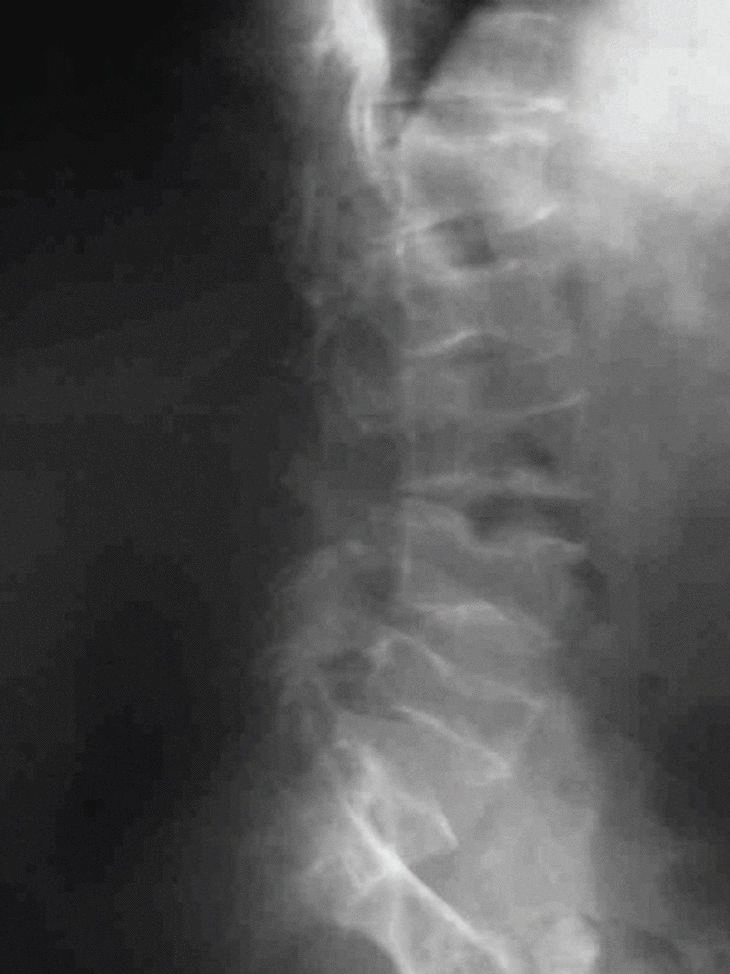

Fig. 5. Radiografía de columna lateral dorso-lumbar, en la que se observan varias deformidades vertebrales.

Es de destacar, en primer lugar, las numerosas fracturas sufridas, siendo una complicación habitual a lo largo de su vida. De hecho, la madre del paciente renunció a contabilizar las mismas al llegar a las 40 en los primeros 9 años de su vida. El paciente tiene una estatura corta, condicionada tanto por la existencia de múltiples deformidades vertebrales, que pueden observarse en la figura 5, como por esta forma clínica de OI que cursa con baja estatura.